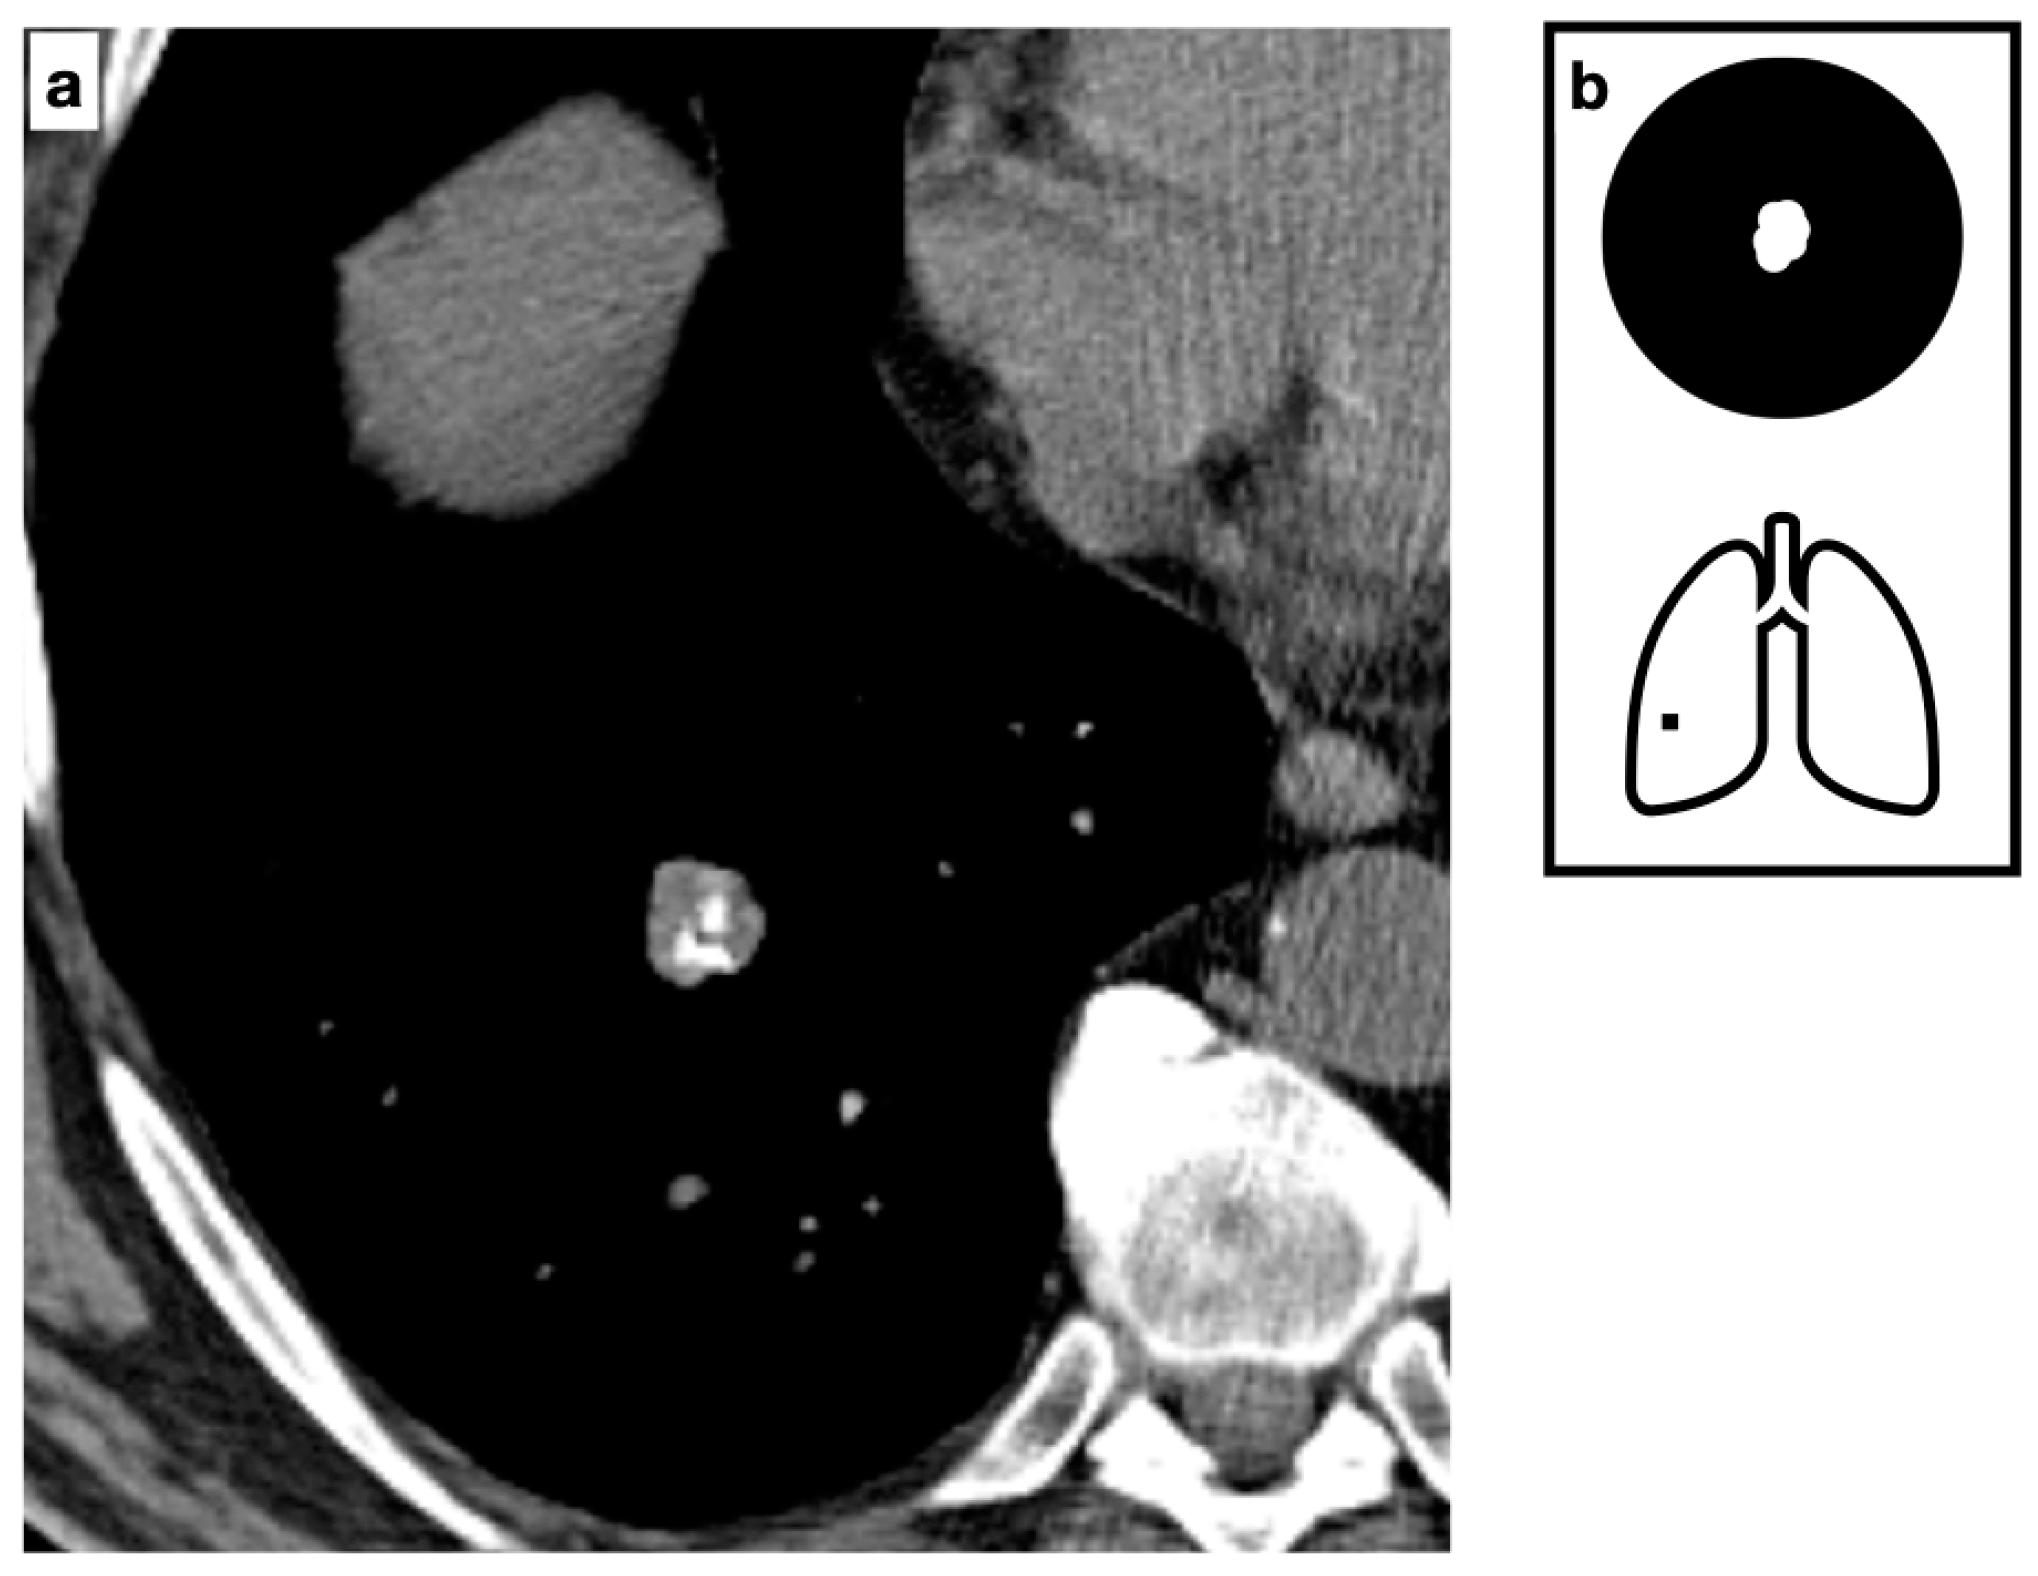

Figure 2.

Composite image from a CT scan demonstrating a solitary small, well-defined nodule with smooth margins, fat-content and typical pop-corn calcifications. The presence of both intralesional fat and calcifications is considered definitively diagnostic for hamartoma (a). Pattern of calcification (b).